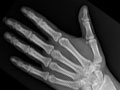

Los huesos o las articulaciones podrían mostrar señales de daño a causa de una enfermedad, como osteoporosis, artritis reumatoide, osteoartritis, gota o enfermedad de Paget. Vea imágenes de artritis reumatoide en los pies y artritis reumatoide en las manos.